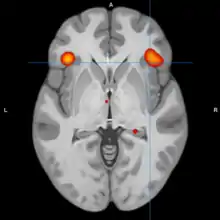

A model of functional neuroanatomy produced by a workgroup led by Stephen M. Strakowski concluded that bipolar was characterized by reduced connectivity, due to abnormal pruning or development, in the prefrontal-striatal-pallidal-thalamic-limbic network leading to dysregulated emotional responses. This model was supported by a number of common neuroimaging findings. Dysregulation of limbic structures is evinced by the fact that hyperactivity in the amygdala in response to facial stimuli has been consistently reported in mania.[33] While amygdala hyperactivity is not a uniform finding, a number of methodological challenges could explain discrepancies. As most studies utilize fMRI to measure blood-oxygen-level dependent signal, excess baseline activity could result in null findings due to subtraction analysis. Furthermore, heterogenous study design could mask consistent hyperactivity to specific stimuli. Regardless of directionality of amygdala abnormalities, as the amygdala plays a central role in emotional systems, these findings support dysfunctional emotional circuits in bipolar. A general reduction in ventrolateral prefrontal cortex activity is observed in bipolar, and is lateralized with regard to mood (i.e., left-depression, right-mania), and may underlie amygdala abnormalities. The dorsal ACC is commonly under-activated in bipolar, and is generally implicated in cognitive functions, while the ventral ACC is hyperactive and implicated in emotional functions. Combined, these abnormalities support the prefrontal-striatal-pallidial-thalamic limbic network underlying dysfunction in emotional regulation in bipolar disorder.[34] Strakowski, along with DelBello and Adler have put forward a model of "anterior limbic" dysfunction in bipolar disorder in a number of papers.[35][36][37][38][39]

Studies examining resting blood flow, or metabolism generally observed abnormalities dependent upon mood state. Bipolar depression is generally associated with dlPFC and medial orbitofrontal cortex hypometabolism. Less consistent associations include reduced temporal cortex metabolism, increased limbic metabolism and reduced ACC metabolism. Mania is also associated with dlPFC and OFC hypometabolism. Limbic hypermetabolism is more consistent than in bipolar depression, but the overall study quality is low due to limitations associated with neuroimaging in acutely manic patients.[70] Another review reported that mania is generally associated with frontal/ventral hypoactivation, while depression is generally associated with the opposite. A degree of lateralization with regard to abnormalities has been reported, with mania being associated with the right hemisphere, and depression the left. Trait abnormalities in euthymic patients have been observed, including hypoactivity in the ventral prefrontal cortex, and hyperactivity in the amygdala.[71]

During cognitive or emotional tasks, functional neuroimaging studies, consistently find hyperactivation of the basal ganglia, amygdala, and thalamus. Prefrontal abnormalities are less consistently reported, although hyperactivation in the ventral prefrontal cortex is a fairly consistent finding.[72] Hyperactivity in the amygdala and hypoactivity in the medial and ventral prefrontal cortex during exposure to emotional stimuli has been interpreted as reflecting dysfunction in emotional regulation circuits. Increased effective connectivity between the amygdala and orbitofrontal cortex, and elevated striatal responsiveness during reward tasks have been interpreted as hyper-responsiveness in positive emotion and reward circuitry. The abnormal activity in these circuits has been observed in non-emotional tasks, and is congruent with changes in grey and white matter in these circuits.[73] Neural response during reward tasks differentiates unipolar depression from bipolar depression, with the former being associated with reduced neural response and the latter being associated with elevated neural response.[74] An ALE meta analysis of functional neuroimaging comparing adults and adolescents found a larger degree of hyperactivity in the inferior frontal gyrus and precuneus, as well as a larger degree of hypoactivity in the anterior cingulate cortex in adolescents relative to adults[75]